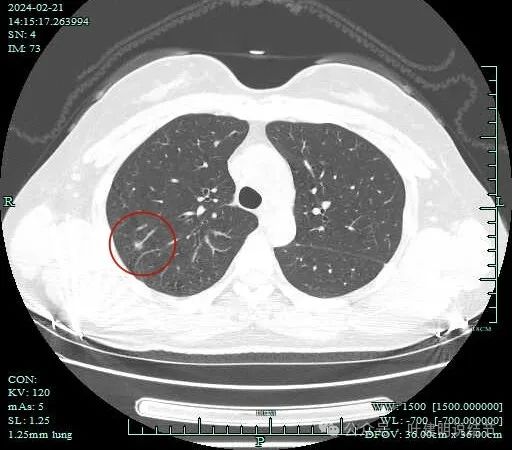

再看2024年2月病灶最明显层面的影像截图:

2024年2月时病灶整体上看密度仍较低,实性的成分就是点状。当然扫描条件也有所不同,可能一定程度影响对比。